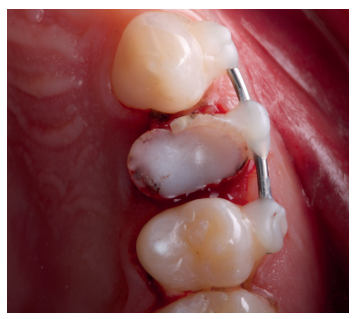

Una vez se hubo posicionado el diente 2 mm supragingival, se procedió a la ferulización con alambre de acero a los dientes adyacentes (Figuras 3 y 4) y la eliminación de cualquier tipo de oclusión, utilizando topes oclusales en los segundos molares inferiores. La ferulización se mantuvo durante dos semanas, coincidiendo con el momento de la endodoncia (Figura 5). El paciente fue citado para las revisiones periódicas y posteriormente para la rehabilitación del diente, una vez hubieron concurrido 6 semanas desde la extrusión, en las que se haya obtenido una cicatrización de los tejidos de soporte supracrestales10. En este momento, tras comprobar signos clínicos, periodontales y radiográficos saludables, se citó al paciente para el tallado y la confección mediante flujo digital (Cerec® System) de una endocorona de disilicato de litio (e.max®, Ivoclar Vivadent). El acondicionamiento de la corona se realizó con ácido fluorhídrico y silano, y para la cementación se utilizó cemento de resina (Calibra®, Dentsply Sirona).

adyacentes, tras la extrusión quirúrgica.